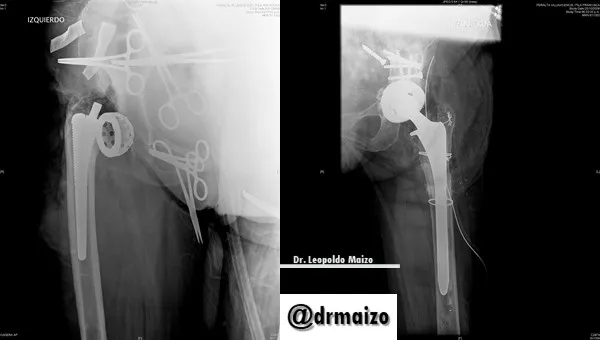

The head and femoral neck resection technique was described by Girdlestone in 1920 as a palliative treatment in patients with hip tuberculosis. This name is still used today to designate the removal of hip prostheses with cement and the regularization of the proximal portion of the remaining femur, when removal is required.

The majority of studies have shown success in controlling hip infections using the Girdlestone technique. Given the characteristics of the patients, they are often accompanied by a high mortality rate in the postoperative period and 7-62% during the first month after surgery.

With regard to the assessment of the functional situation in which these patients remain after the intervention, there are fewer jobs and those that are difficult to compare because they study young and old patients and use different scales to assess residual function.

In patients with Girdlestone there is the disadvantage of evaluating the deformity and the articular range which, due to the characteristics of this operation, tend to be extreme.

Dr. Leopoldo Maizo - Orthopedic Surgeon